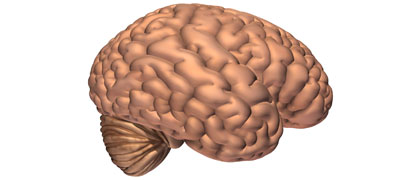

Lippincott Williams & Wilkins. Reproduced with permission from Neurosurgery 1998; 43(4): 877-8.